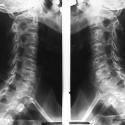

Pour confirmer le diagnostic, votre médecin vous fera faire des radios qui lui permettront de voir si vous avez des excroissances osseuses autour des articulations. Ce sera alors le signe que l’arthrose est bien installée.

- arthrose cervicale : douleurs intermittentes dans la nuque, l’épaule, le bras